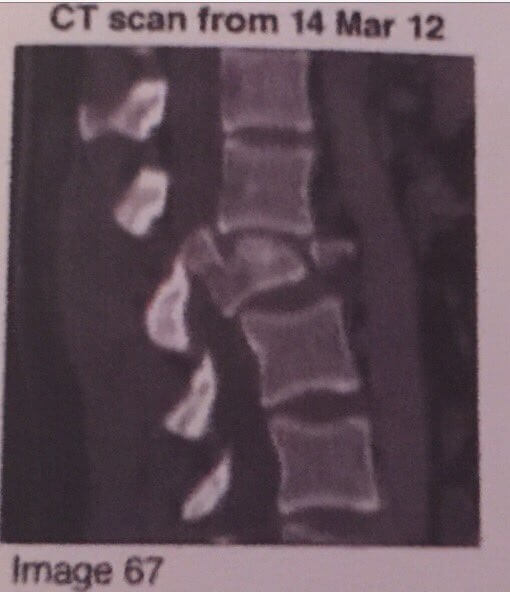

She grabbed the home phone and called for help. Michael was taken to Sunnybrook hospital for treatment. Four hours after the accident he was in surgery to have his L2 and L3 fused along with having two rods inserted into his back to support his spine.

L3 to T11 of the spin are responsible for most of your lower body and Michael’s was in bad shape. The doctors had discovered that he also had a collapsed lung a nick on the spinal cord. This damage left Michael paralyzed from the waist down.